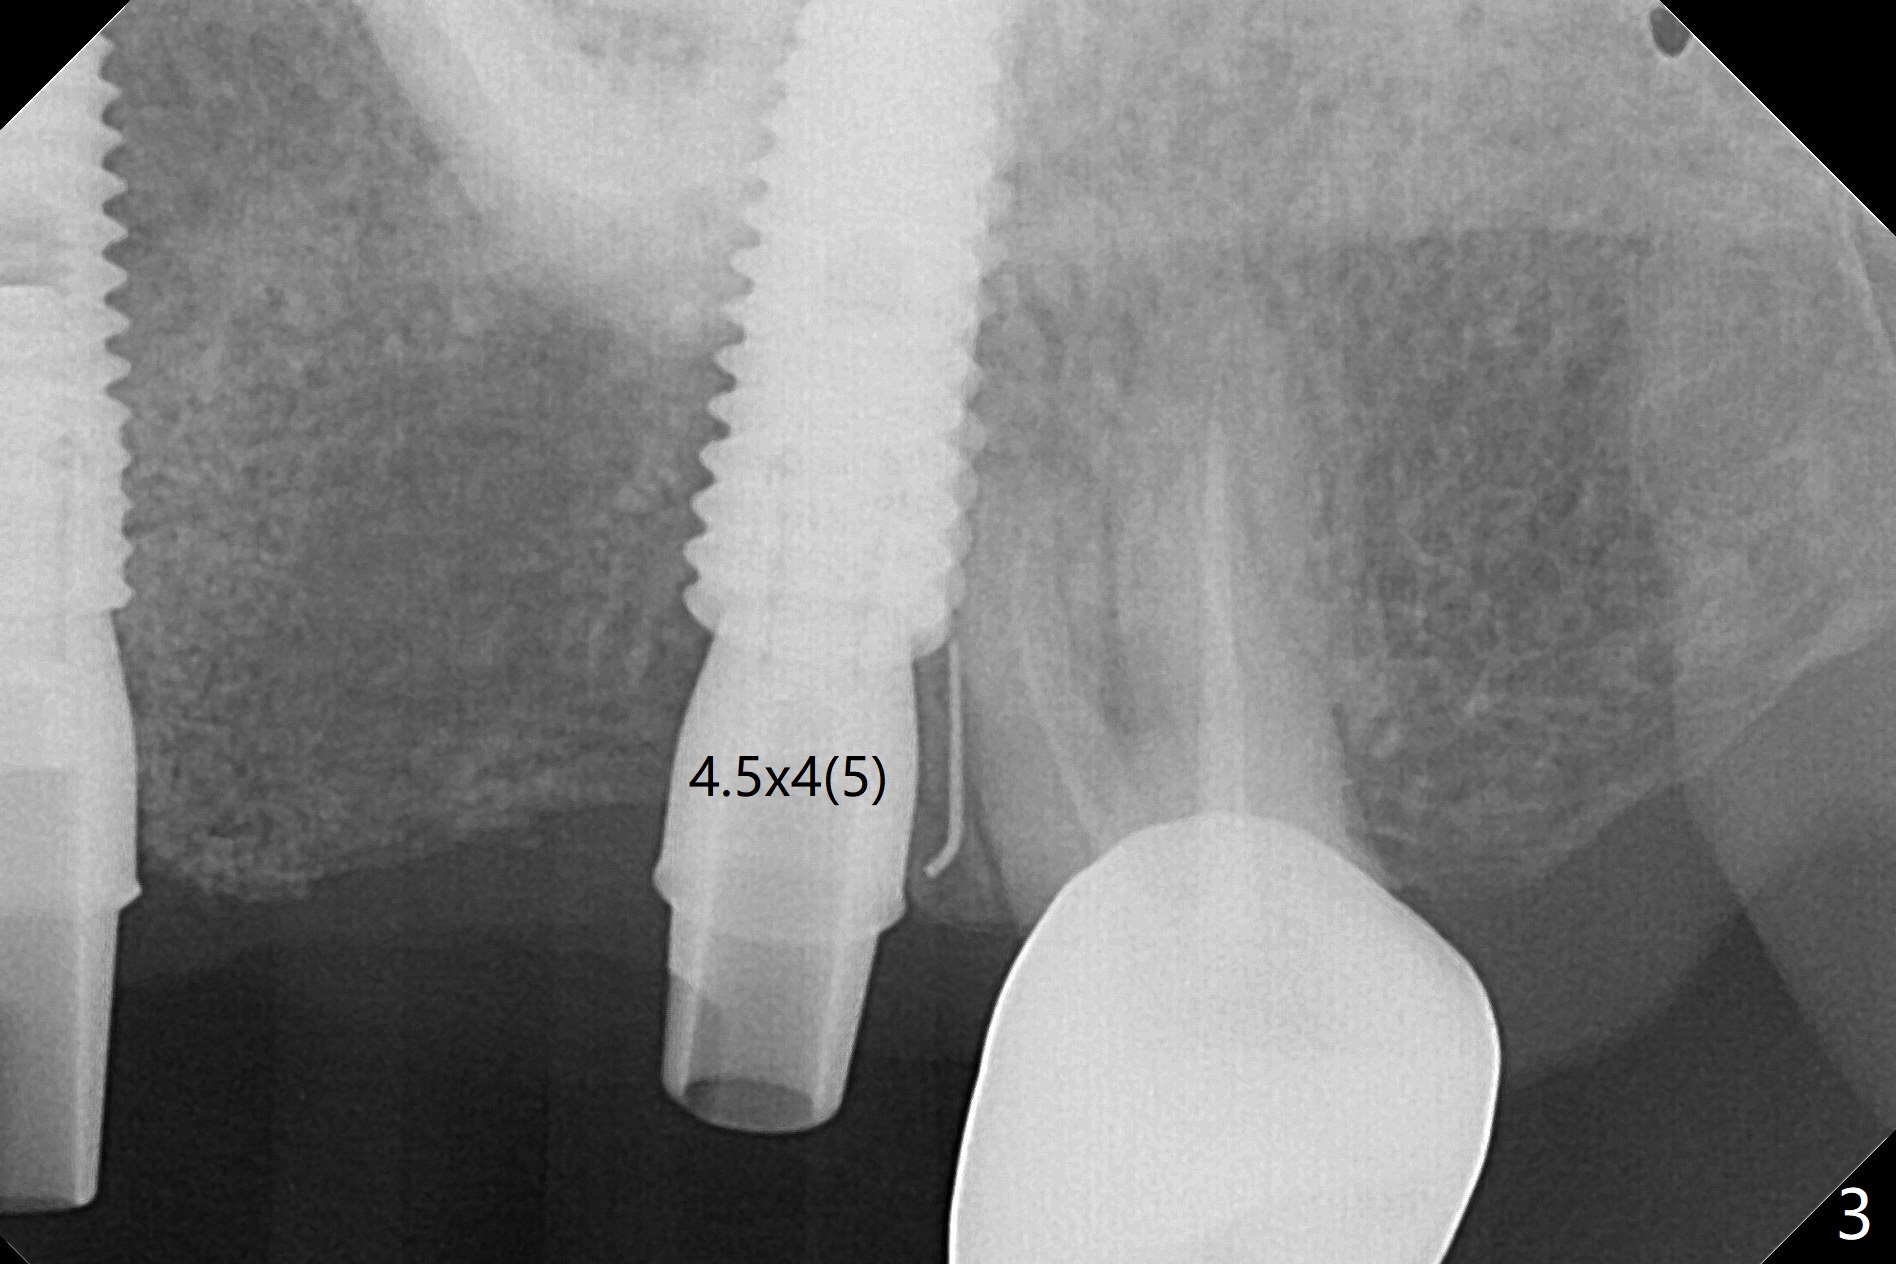

A 55-year-old woman had Hiossen implants (4x13, 5x13 mm) placed at #12 and 14 in China > 6 months (Fig.1,2). The fixtures are placed deep and un-parallel mesiodistally. After SRP UL, the implant at #12 is uncovered, followed by 4.6 and 5.5 mm profile drills and 5.5x7 mm IS healing abutment. The healing abutment at #14 is changed from 5x7 mm to 6.8x7 mm for easy impression later on. Due to coronavirus, the patient returns 8 months later. Oral hygiene is poor. The gingival cuffs at #12 and 14 are erythematous and edematous. UF cemented abutments have to be placed (Fig.3-5) because of equi-gingival fracture of #3 and 4 splinted crowns. In fact the straight abutments are not parallel buccopalatally. Buccoocclusal reduction is done at #12 for provisional FPD. SRP will be performed with #11 DL composite prior to impression.